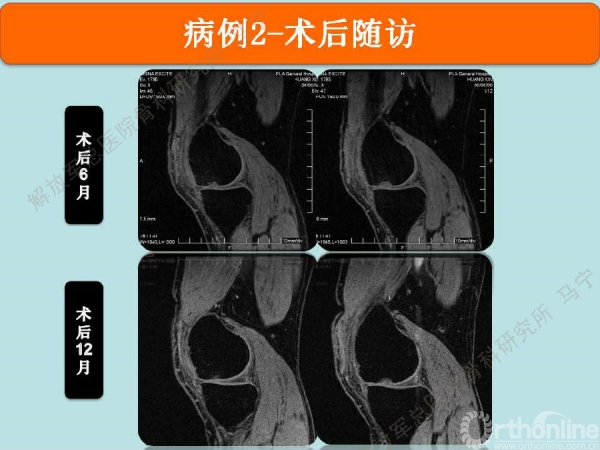

术后6个月仍能看到修复区的软骨,术后12个月软骨仍在继续修复,修复的厚度满意。

术后5年半,目前膝关节无明显症状。MRI显示修复区的软骨仍有一定的厚度。损伤的软骨区没有继续扩大。